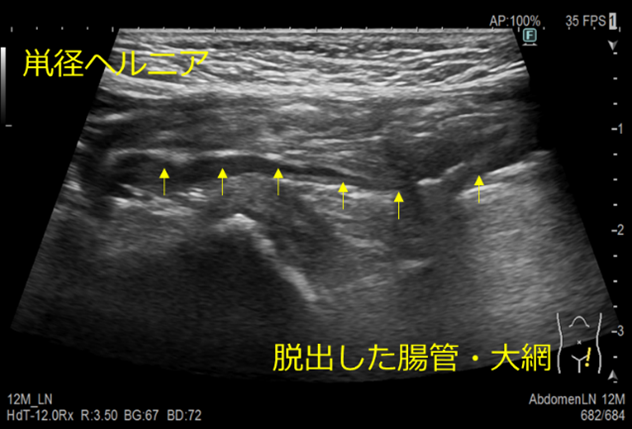

体表の皮下病変の有無や性状、鼡径ヘルニアの有無の観察をします。

鼡径ヘルニアとは

ヘルニアとは、先天的・後天的な原因で生じた組織の間隙から、臓器や組織が脱出している状態です。

鼠径靱帯頭側で鼠径部に脱出する外ヘルニアのことを鼡径ヘルニアといいます。